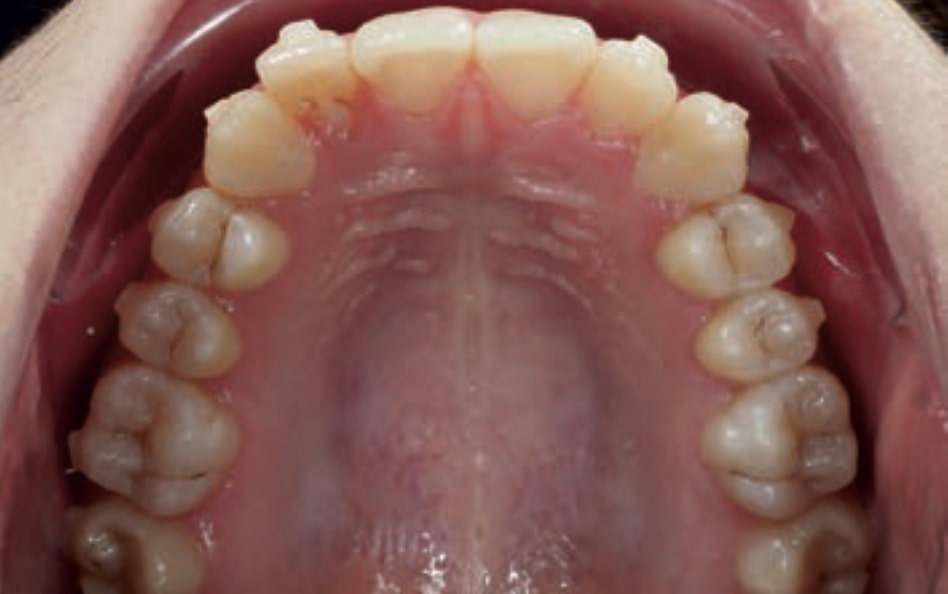

Chief complaint: The patient, a 19-year-old woman, was evaluated to undergo orthodontic treatment using the Angel Aligner Pro system. She presents with a skeletal Class III, mesofacial, with a dental Class III malocclusion and a 2 mm deviation of the lower midline to the left. Teeth 33 and 43 are out of the arch and cortical bone, with a crossbite issue on tooth 33. Fortunately, no functional issues affecting swallowing or breathing have been detected. The patient’s motivation for starting treatment was a general review of her dental and aesthetic health. The soft tissue analysis reveals mandibular protrusion that influences her facial profile. This diagnosis highlights the need for a comprehensive approach to address dental and skeletal misalignments, improving both the patient’s functionality and facial aesthetics.

• Dental Class III, 2 mm deviation of the lower midline to the left. 33 and 43 out of the arch and the cortical bone.

• Crossbite of 33.

• Distalize third and fourth quadrant

• Distalization of the Third and Fourth Quadrants: Move the teeth distally in these quadrants to achieve a Class I relationship using the A8 protocol, improving the patient’s dental alignment and occlusion.

• Improve the Root Position of Teeth 33 and 43: Optimize the position of the roots of teeth 33 and 43 in relation to the cortical bone to ensure adequate bone support and long-term stability.